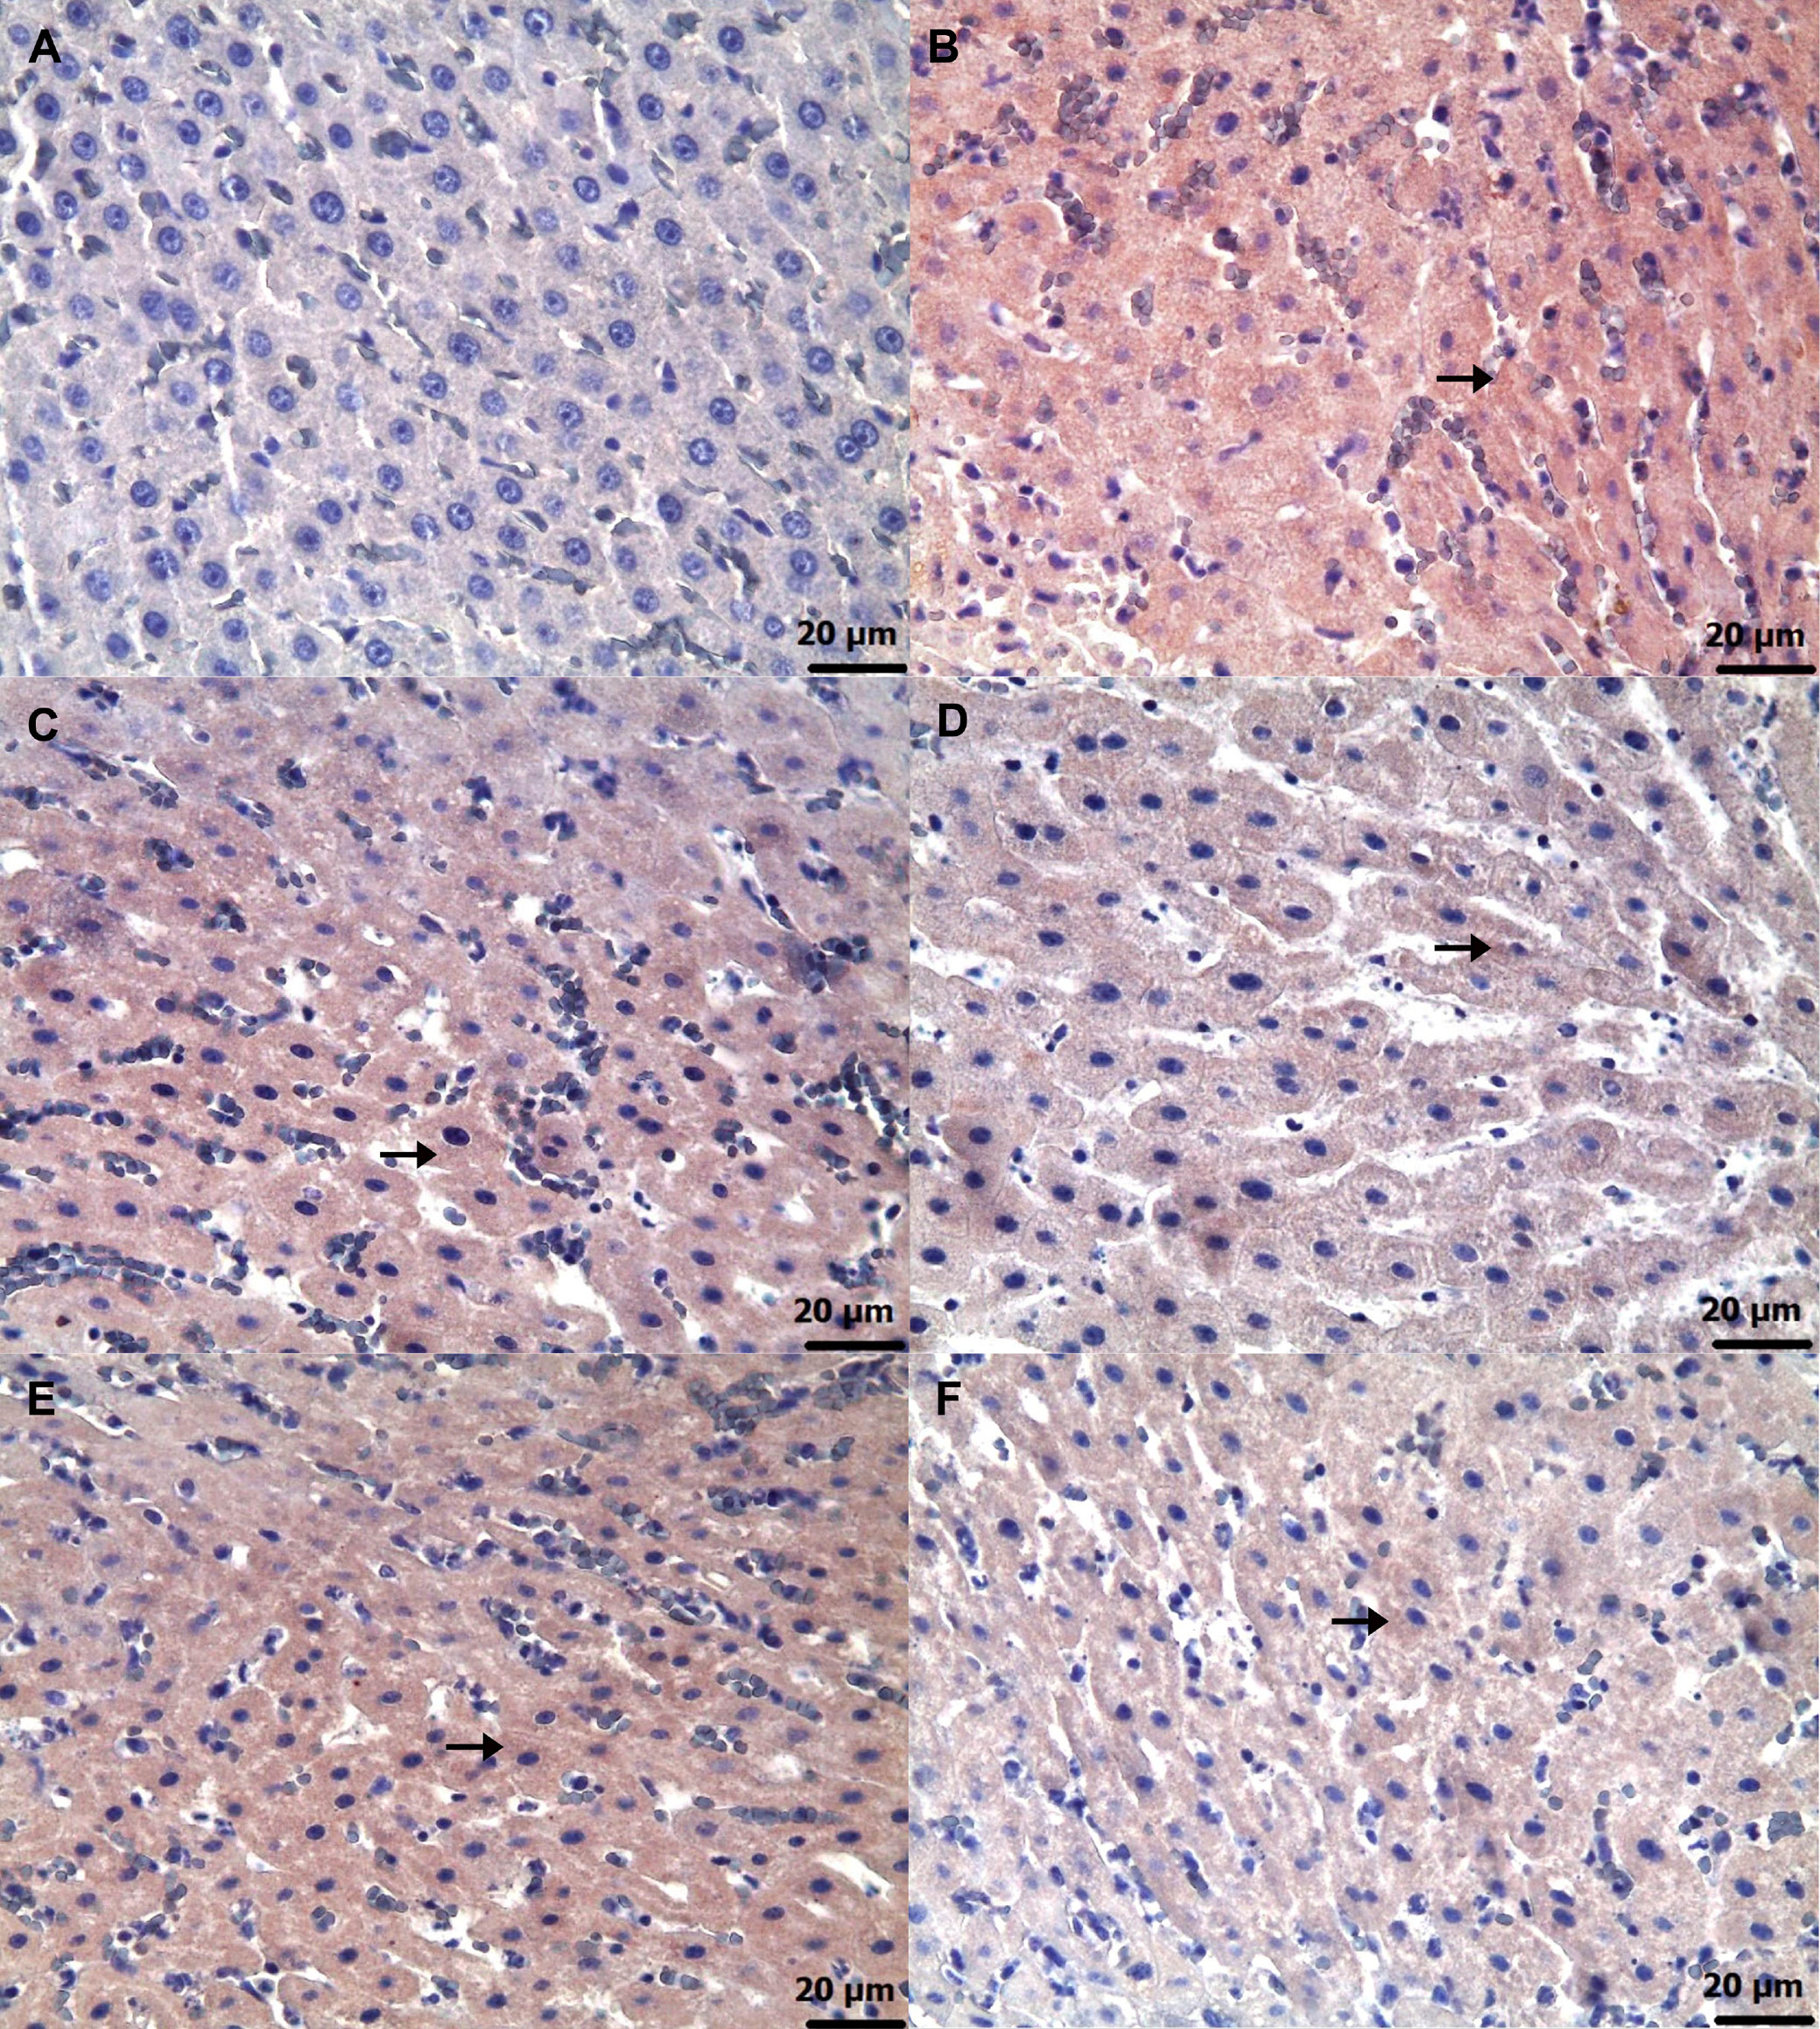

Immunohistochemical examinations for caspase-3 (Figure 6) and TNF-α (Figure 7) revealed statistically significant differences between the groups (Table 5, Table 6; p < 0.05). No significant caspase-3 and TNF-α immunopositivity was found in the HG group. Among the treatment groups, strong caspase-3 and TNF-α immunopositivity was observed in the ADG group, moderate immunopositivity in the AAG-2 and RAG groups, and mild immunopositivity in the AAG-5 and RAA-2 groups.

Furthermore, the biochemical and histopathological findings observed in the amiodarone, ATP, resveratrol, ARC, and healthy rat groups were consistent with the corresponding immunohistochemical results. Grade 3 level caspase-3 and TNF-α immunopositivity was detected in the liver of the group receiving amiodarone alone. It was observed that this caspase-3 and TNF-α immunopositivity was alleviated to grade 2 in the 2 mg/kg ATP and resveratrol groups, and to grade 1 in the 5 mg/kg ATP and 2 mg/kg ATP + resveratrol groups. A recent study reported that amiodarone induces apoptosis by causing caspase-3 activation in liver cells.41 These literature data support our immunohistochemical caspase-3 findings. Amiodarone decreases intracellular ATP and Ca2 + in hepatocytes, causing endoplasmic reticulum stress and lipid accumulation.42 The toxic effects of amiodarone on the liver consist of mitochondrial toxicity, apoptosis and necrosis. Mitochondrial damage leads to activation of caspase-9, and binding of death receptors activates caspase-8. Activation of both caspase-9 and caspase-8 leads to propagation of the cascade of downstream effector caspases, including caspase-3. In conclusion, amiodarone induces apoptosis in hepatocytes by activating the mitochondrial apoptotic pathway, involving caspase-2, -3 and -9.42, 43 It has been previously demonstrated that amiodarone causes immune dysregulation in liver tissue, which leads to an increase in the proportion of Th17 and Th1 cells and causes a significant increase in inflammatory factors such as TNF-α.44 In hepatocytes, mitochondria play a central role in linking caspase-8 activation to caspase-9, ultimately leading to the activation of effector caspases such as caspase-3 and caspase-7. Loss of mitochondrial membrane potential, generation of ROS, formation of the mitochondrial permeability transition pore and release of cytochrome C are critical for TNF-α-induced hepatocyte apoptosis.45